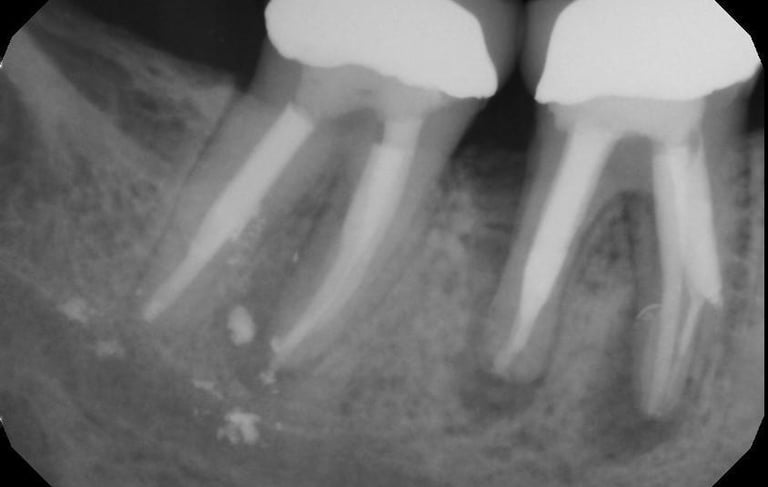

Se identifica si hay fracturas en la raíz del diente, que pueden causar dolor, infecciones o problemas de estabilidad dental. Se utilizan radiografías y exámenes clínicos para este diagnóstico.

Evaluación de fracturas radiculares

Se analiza el estado de dientes que han recibido tratamientos endodónticos anteriores para verificar su éxito y determinar si se necesita un retratamiento.

Evaluación de dientes con tratamientos previos